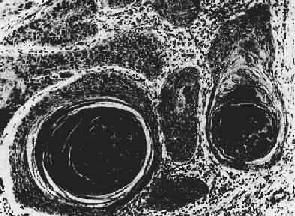

图7-13 腺癌(胃) 癌细胞排列紊乱,多层,形成大小不等、形状不规则的腺样结构,浸润于胃壁组织内 (2)粘液癌(mucoid carcinoma):又称为胶样癌(colloid carcinoma),常见于胃肠。镜下,初时粘液聚积在癌细胞内,将核挤向一侧,使该细胞成印戒状, 故一般称之为印戒细胞(signet-ring cell)。以后粘液堆积在腺腔内,并可由于腺体的崩解而形成粘液池。此时,往往可见于小堆或散在的印戒状癌细胞漂浮其中。肉眼观,癌组织呈灰白色,湿润,半透明如胶冻样,胶样癌因而得名。 (3)实性癌(solid carcinoma):或称单纯癌(carcinoma simplex),属低分化的腺癌,恶性程度较高,多发生于乳腺,少数可发生于胃及甲状腺。癌巢为实体性,无腺腔样结构,癌细胞异型性高,核分裂像多见。有的癌巢小而少,间质结缔组织多,质地硬,称为硬癌(scirrhous carcinoma)(图7-14)。有的则癌巢较大较多,间质结缔组织相对较少,质地如脑髓,称为髓样癌(medullary carcinoma)。